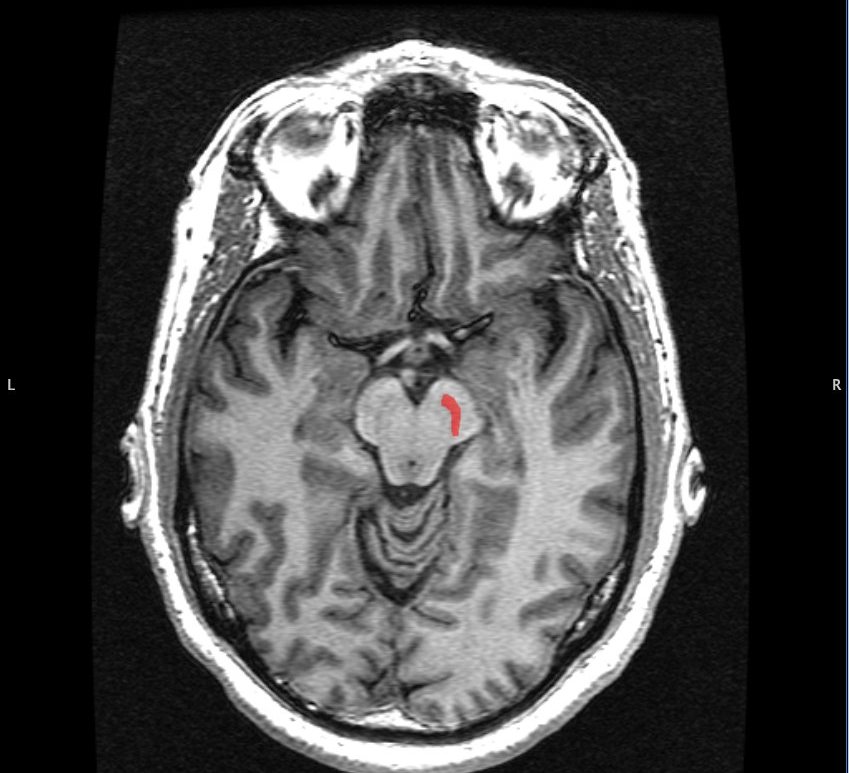

Author: Amal Bilal, Class of 2028 Neurocardiology is a new and emerging field that examines the heart-brain interaction in the context of health and disease. Conditions such as stroke and cardiac arrhythmia are connected by the heart-brain axis: a network of neural, vascular, and physiological signals. Early and accurate detection of abnormalities along this axis is essential for improving patient outcomes. Stony Brook Medicine researcher … Continue reading Clinical Applications of Artificial Intelligence in Neurocardiology